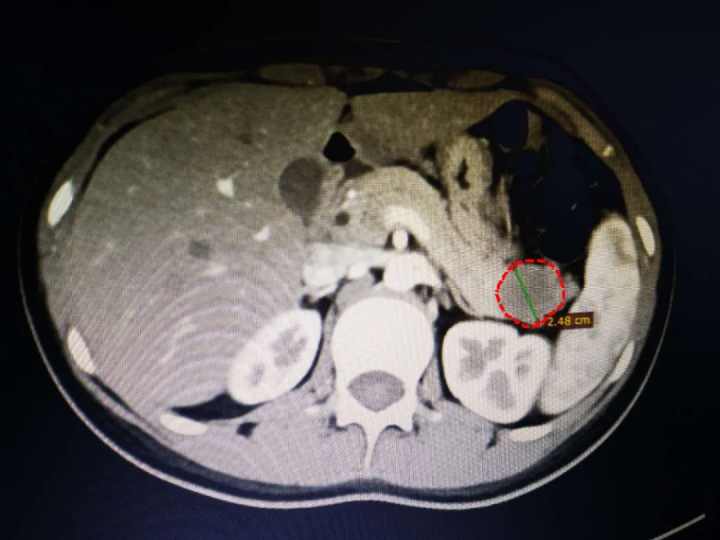

几经辗转,一家人找到了树兰(杭州)医院,入住肝胆胰外科。完善相关检查后,考虑小姑娘患的是,胰腺实性假乳头状肿瘤。肿瘤直径2-3厘米,位于胰尾部,紧贴肾脏与脾脏。

但好在这种肿瘤是低度恶性肿瘤,早期手术切除的话,术后恢复还是不错的。